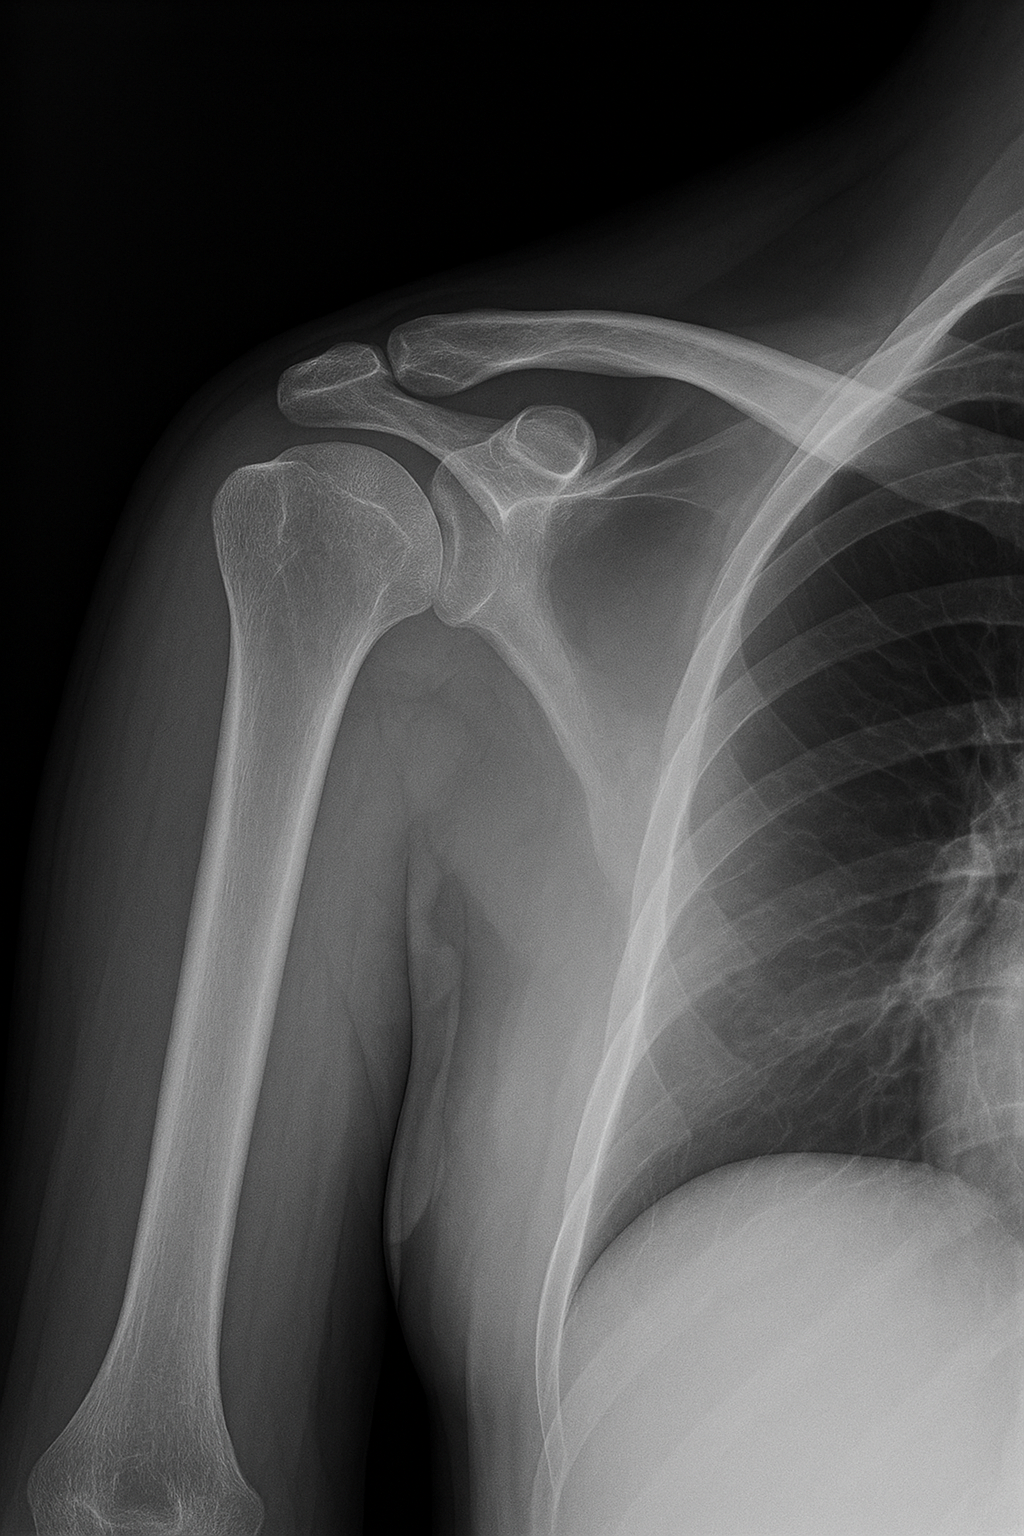

초음파, X-ray 등으로 정확한 진단 후 맞춤 치료를 받으면, 수술 없이도 대부분 일상으로 복귀할 수 있습니다.